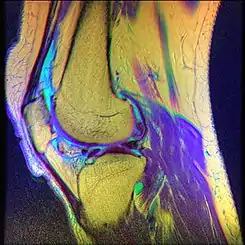

La condromalacia rotuliana también conocida como síndrome femoropatelar, condromalacia patelar o condritis rotuliana es una enfermedad caracterizada por la degeneración de la superficie articular cartílago que constituye la cápsula posterior de la rodilla. Produce malestar o dolor sordo alrededor o detrás de la rótula, y es un padecimiento bastante común entre adultos jóvenes, especialmente jugadores de baloncesto, vóley, fútbol, ciclistas, karatecas, tenistas, remeros, bailarines de ballet, corredores, etc. Los jugadores de rugby son también propensos a esta enfermedad, especialmente quienes juegan en posiciones en las que las rodillas realizan esfuerzos importantes. Asimismo, los alpinistas también son propensos a padecerla, al soportar un gran peso por sus mochilas y sobre todo en nieve.

Puede generarse a partir de una lesión aguda de la rótula o mediante la fricción crónica entre la rótula y la articulación del fémur al mover la rodilla. El diagnóstico de condromalacia corresponde a una rodilla cuya estructura ha sido dañada, mientras que la descripción más genérica de "Síndrome patelo-femoral" se refiere a los estadios iniciales de la enfermedad, en los que los síntomas pueden ser totalmente reversibles.

Diagnóstico

Grados

• Grado 1: En el que existe edema y el cartílago rotuliano ya está reblandecido.

• Grado 2: Fibrilación o alteración en la superficie del cartílago. Esto se ve en las artroscopias como si el cartílago "se deshilachara".

• Grado 3: Fisuración, existiendo ya hendiduras que alcanzan las capas más profundas.

• Grado 4: Ulceración, agravándose las hendiduras anteriores.

• Grado 5: Eburnación, debido a la profundización de la ulceración se llega a afectar el hueso subcondral que tenderá a hipertrofiarse como en la artrosis.